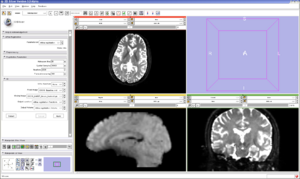

With the images loaded into Slicer, select the Registration-Affine Registration module as shown:

Set the Fixed image to icbm452_atlas_air12_sinc.hdr and the moving image to OAS1_0001_MR1_mpr-1_anon.hdr. The default settings are sufficient to register these images

With the images loaded into Slicer, select the Registration-Affine Registration module as shown:

Set the Fixed image to icbm452_atlas_air12_sinc.hdr and the moving image to OAS1_0001_MR1_mpr-1_anon.hdr. The default settings are sufficient to register these images